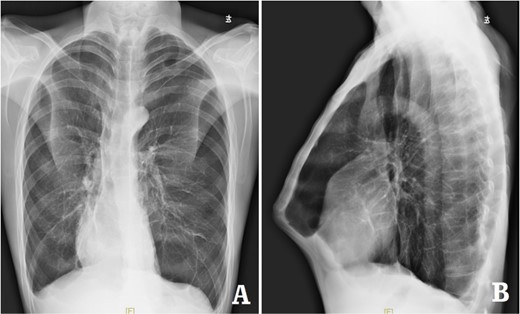

The patient was a 29-year-old male. He was found to have protrusive deformity on the anterior chest wall since childhood. The deformity was not serious in early years, but worsened after adolescence, with the lower part of the sternum protruding at an acute angle. At the age of 25, he developed right spontaneous pneumothorax and received surgical treatment at local hospital, but his thoracic deformity was not treated. As the deformity continued to worsen, which seriously affected the appearance of the chest wall, the patient was admitted to our hospital for surgery. Preoperative physical examination showed that the anterior chest wall was protrusive seriously, with a sharp tip protruding forward. The rib arches on both sides were slightly depressed (Fig. 1). Imaging examination showed that the anterior chest wall was protrusive, and the lower end of the sternum was at the forefront of the protrusion. His heart moved to the right, and the rib arches were slightly depressed (Figs 2–4). The operation was performed under general anesthesia. Two longitudinal incisions were made on both sides of the chest wall respectively. The incisions were located between the front axillary line and the median axillary line, with the length of ~5 cm. The chest wall muscles were dissected to expose the ribs in the incisions. Two tunnels were made on the highest plane of the protrusion, with interval of 3 cm. The tunnels were located in the deep layer of the chest wall muscles and bone structures. Two steel bars were inserted into the tunnels to flatten the front protrusion with their median parts, and then, both ends of the steel bars were fixed on the ribs at the lateral chest wall. The above operation was the main content of Wenlin procedure [1, 2, 5]. After this procedure was completed, the lower part of the chest wall showed obvious depression, especially in the middle of the rib arches. Then, Wung procedure was performed [6]. A third tunnel was made at the plane passing the midpoint of the rib arch, which passes through the bilateral thoracic cavity. The third steel bar was inserted into the tunnel. After the steel bar was rotated and fixed to the ribs, the depression was supported totally. The incisions were closed, and the operation was completed. The deformity of anterior chest wall disappeared completely after the operation (Fig. 5). The operation time was 75 min. The intraoperative bleeding volume was 40 ml. Postoperative X-ray examination showed that the bars position was normal (Fig. 6). He was discharged 7 days after operation. Follow up for 1 year showed satisfactory recovery. The steel bars were taken out 1 year after the operation, and the appearance of the thorax was normal and there was no recurrence (Fig. 7).

X-ray examination after the bars were taken out. (A) Posteroanterior radiograph; and (B) lateral radiograph.